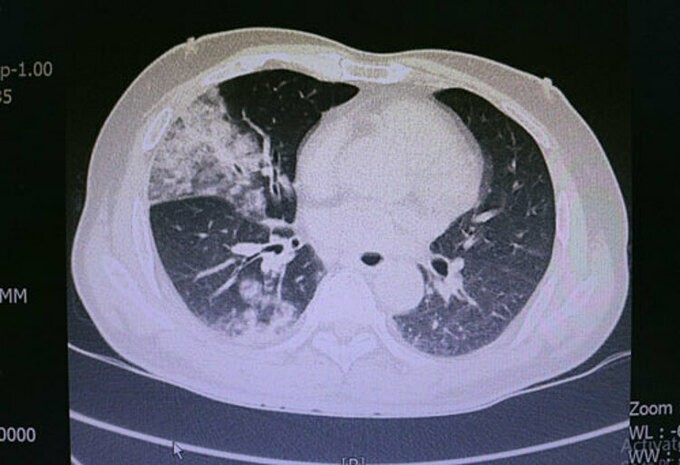

Các bác sĩ Khoa Hồi sức tích cực Nội chẩn đoán bệnh nhân bị sốc nhiễm khuẩn, viêm phổi nặng trên nền bệnh đái tháo đường tuýp 2, nghiện rượu.

Bác sĩ Vũ Công Quân cho biết, thông thường, các trường hợp viêm phổi, nhiễm trùng, tế bào bạch cầu trong máu tăng cao để bảo vệ cơ thể. Riêng bệnh nhân này, các tế bào bạch cầu lại giảm rất nhanh, là sự mất khả năng tự bảo vệ của cơ thể.

Sau khi hội chẩn, các bác sĩ sử dụng kháng sinh mạnh nhất, lọc máu liên tục, thở máy và kết hợp với các biện pháp điều trị nội khoa. Bệnh nhân hiện vẫn trong tình trạng nguy kịch, tiên lượng thời gian điều trị kéo dài và chi phí rất tốn kém.

Theo bác sĩ, người nghiện rượu nhiều năm, đặc biệt đã ở giai đoạn xơ gan, nếu bị viêm phổi thì bệnh thường diễn tiến rất nhanh, tiên lượng nặng. 70-80% bệnh nhân có thể tử vong.